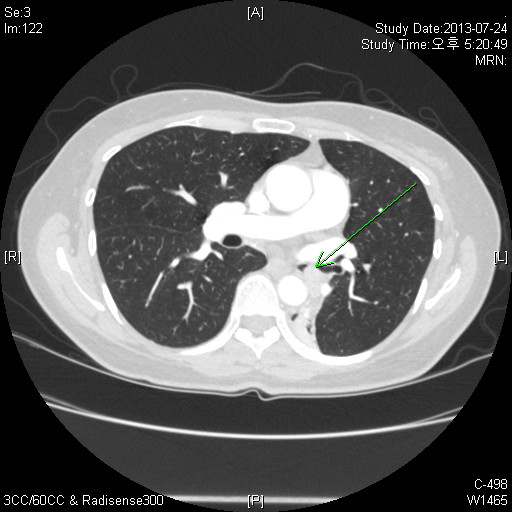

CXR»ó È®ÀÎÇÒ ¼ö ÀÖ´Â ¼Ò°ß, Á¤´äÀº LLL atelectasisÀÔ´Ï´Ù.

Chest PA»ó ½ÉÀå°ú Áß÷µÇ¾î »ï°¢Çü ¸ð¾çÀÇ À½¿µÀÌ º¸ÀÔ´Ï´Ù. ÁÂÃø Æó¹®ÀÌ Á» ³·¾ÆÁö°í ÁÂÇÏ¿± Æóµ¿¸ÆÀÌ Àß º¸ÀÌÁö ¾Ê´Â °æ¿ì°¡ ¸¹½À´Ï´Ù. lateral¿¡¼­´Â major fissure°¡ ÈĹæÀ¸·Î À̵¿ÇÒ ¶§ ÀǽÉÇÒ ¼ö ÀÖ°Ú½À´Ï´Ù.

CT¹× FOBÀÇ ¼Ò°ßÀ» º¸½Ã¸é LLL¸¦ obstructingÇϰí Lt main bronchus±îÁö protruding ÇÏ´Â mass°¡ °üÂûµË´Ï´Ù. FOB·Î biopsy»ó Carcinoid tumor°¡ Áø´ÜµÇ¾ú½À´Ï´Ù.

LLL atelectasis

Obstructing endobronchial tumor , Carcinoid tumor µÇ°Ú½À´Ï´Ù.